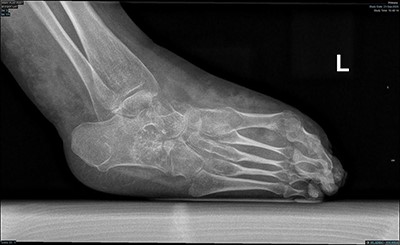

Examination of the left lower limb revealed hemihypertrophy and superficial dilated vessels. There was a rigid pes cavus with equinus deformity in the left foot (Fig. 1). Neurological examination revealed the power of left foot dorsiflexion/plantarflexion was zero out of five and inversion/eversion was two out of five. Reflexes, tone and sensations in both limbs were normal. The vascular exam showed palpable dorsalis pedis and femoral pulses bilaterally. It was difficult to palpate left popliteal pulses. The posterior tibial pulse was absent bilaterally. The right foot examination was unremarkable otherwise.

Magnetic resonance imaging (MRI) brain and whole spine were ordered for her due to the neurological pattern of the disease. The MRI showed T4–T5 posterior fusion, there were no other neurological lesions. For evaluation of the varicose veins, vascular consultation was obtained, and Doppler ultrasound was ordered, which showed absent popliteal deep veins. Radiography of the left foot revealed marked cavus as well as hindfoot and forefoot varus. Also, it showed soft tissue swelling, reduction in bone density, and no evidence of fracture or dislocation or tarsal coalition (Fig. 2). The right foot radiograph was unremarkable apart from mild hallux valgus deformity (Fig. 3).

Lateral weight bearing radiograph showing severe pes cavus with osteopenia and soft tissue swelling.